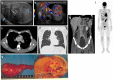

Pre- and post-pubertal testicular tumors are two distinct entities in terms of epidemiology, diagnosis and treatment. Most pre-pubertal tumors are benign; the most frequent are teratomas, and the most common malignant tumors are yolk-sac tumors. Post-pubertal tumors are similar to those found in adults and are more likely to be malignant. Imaging plays a pivotal role in the diagnosis, staging and follow-up. The appearance on ultrasonography (US) is especially helpful to differentiate benign lesions that could be candidates for testis-sparing surgery from malignant ones that require radical orchidectomy. Some specific imaging patterns are described for benign lesions: epidermoid cysts, mature cystic teratomas and Leydig-cell tumors. Benign tumors tend to be well-circumscribed, with decreased Doppler flow on US, but malignancy should be suspected when US shows an inhomogeneous, not-well-described lesion with internal blood flow. Imaging features should always be interpreted in combination with clinical and biological data including serum levels of tumor markers and even intra-operative frozen sections in case of conservative surgery to raise any concerns of malignity. This review provides an overview of imaging features of the most frequent testicular and para-testicular tumor types in children and the value of imaging in disease staging and monitoring children with testicular tumors or risk factors for testicular tumors.